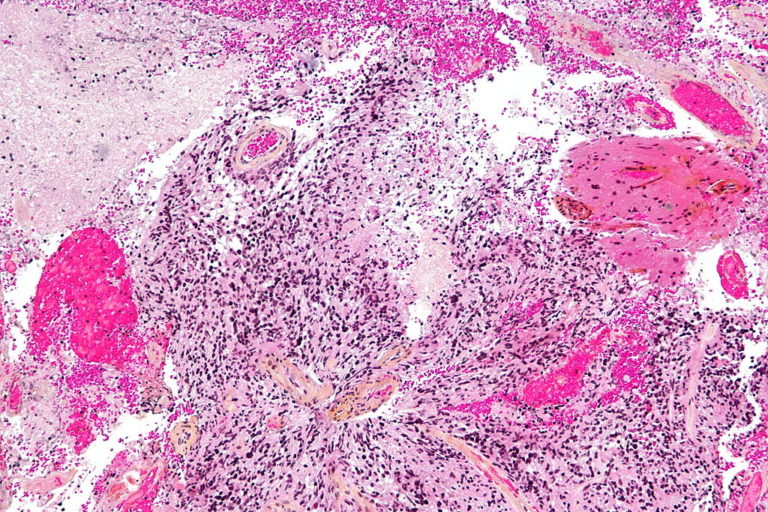

Η ανακάλυψη θα μπορούσε να ωφελήσει τους 2.500 ανθρώπους ετησίως στο Ηνωμένο Βασίλειο που διαγιγνώσκονται με γλοιοβλάστωμα, την πιο κοινή μορφή καρκίνου του εγκεφάλου και επίσης μία από τις πιο επιθετικές. Οι άνθρωποι με τη νόσο ζουν κατά μέσο όρο μόλις 12-18 μήνες μετά τη διάγνωση, ενώ ορισμένοι ακόμη λιγότερο.

Το εμβόλιο είναι μια μορφή ανοσοθεραπείας, κατά την οποία το ανοσοποιητικό σύστημα του οργανισμού προγραμματίζεται να εντοπίζει και να επιτίθεται στον όγκο. Είναι το πρώτο που αναπτύχθηκε για την αντιμετώπιση των όγκων του εγκεφάλου.